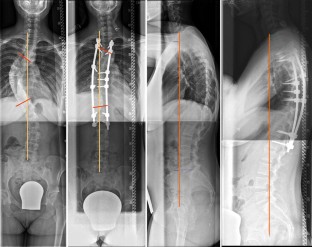

Abb. 1

Ziel der vorliegenden Studie ist es, den Effekt verschiedener dorsaler Operationstechniken auf das sagittale Profil zu untersuchen. Retrospektiv wurden 36 Patienten mit thorakaler idiopathischen Adoleszentenskoliose eingeschlossen, welche mittels dorsaler Korrekturspondylodese versorgt wurden. Unter Berücksichtigung verschiedener Korrekturprinzipien wurden die Patienten in Subgruppen eingeteilt (A Pedikelschraube, B Langkopfpedikelschraube, C Langkopfpedikelschraube mit Ponte-Osteotomien). Standardröntgenaufnahmen der ganzen Wirbelsäule im Stehen wurden vor und mindestens 2 Jahre nach dorsaler Korrektur angefertigt. Eine Subgruppenanalyse wurde zur Detektierung von Gruppenunterschieden vorgenommen.

The purpose of this study was to evaluate the effects of different posterior correction techniques on sagittal profile and balance. A total of 36 consecutive patients with thoracic AIS, who were treated with selective thoracic posterior correction were included in this retrospective study. The patients were further assigned to three different subgroups according to different surgical strategies: A: pedicle screws, B: long-head pedicle screws and C: additional Ponte osteotomy. Standardized radiographs in the standing position of the whole spine in two planes were evaluated before and at least 2 years after correction for all patients and a subgroup analysis was done to identify differences between the three groups.